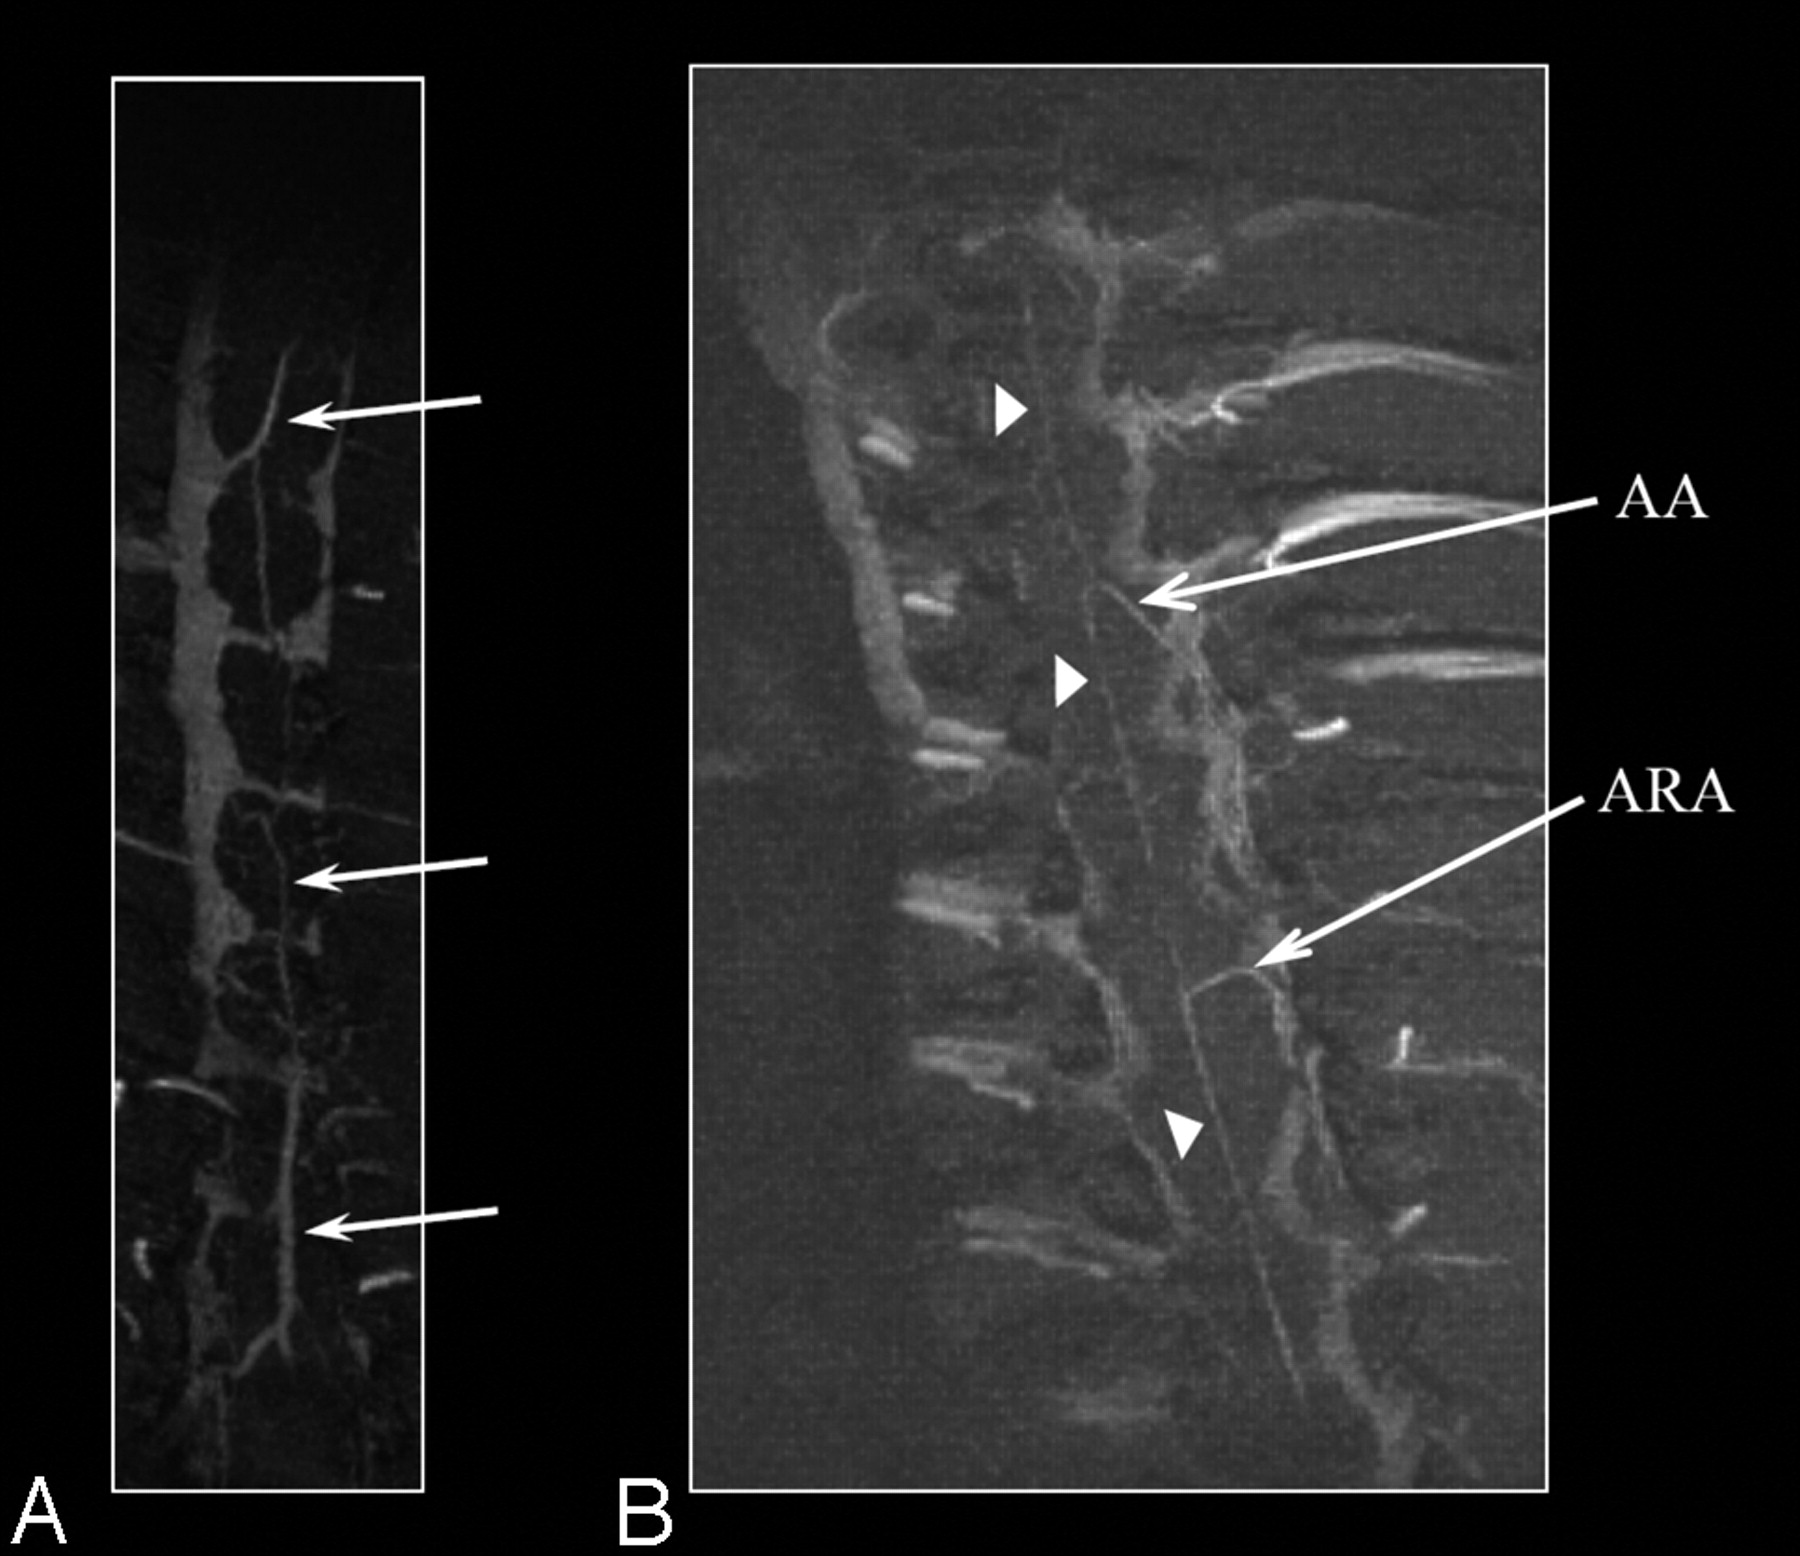

Axial images from the post–liposomal-Gd volume acquisition of the midthoracic spine were also reviewed (Fig 3). The HV is clearly seen in this image. The descending aorta and a section of the inferior vena cava are also visible. In addition, unnamed perforating vessels are identified penetrating the ventral spinal cord (Fig 3B, -D). Artifacts due to the presence of the surgically implanted radio-frequency coil within the soft tissues of the back are also visible in all the images. The PSV, anterior spinal artery (ASA), and radicular arteries (including presumably the artery of Adamkiewicz with its characteristic hairpin turn) are identified on the MIP images generated in the coronal plane (Fig 4).

Coronal MIP images of the thoracolumbar spine region obtained with liposomal-Gd. The posterior spinal vein (PSV) is clearly seen in A (arrows). The anterior spinal artery (arrowheads), the artery of Adamkiewicz (AA) and an accessory anterior radicular artery (ARA) can be clearly seen in B.